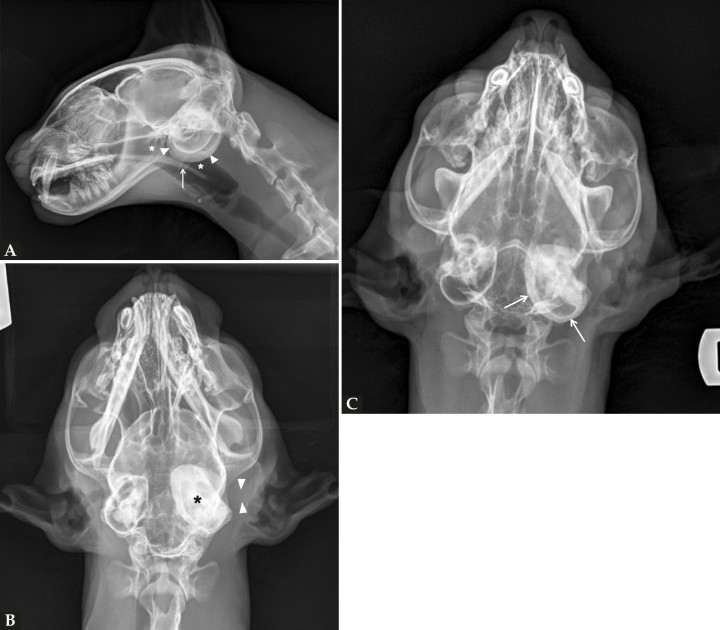

Se realizó un estudio radiográfico de la cabeza del paciente, incluyendo una proyección lateral (Fig. 1A), dorsoventral (Fig. 1B) y rostro 10º ventro-dorsocaudal oblicua (R10ºVCdD) con boca cerrada (Fig. 1C).

Radiografías de la cabeza de un gato maine coon de un año de edad. (A) Proyección lateral. (B) Proyección dorsoventral. (C) Rostro 10º ventro-dorsocaudal oblicua.

En la proyección lateral (Fig. 2A) se observa con buena definición y sin alteraciones la nasofaringe y paladar blando. Una de las bullas timpánicas (BTs) se aprecia aumentada de opacidad con engrosamiento de su pared ventral, no pudiéndose discernir de qué BT se trata al estar superpuestas. En la proyección dorsoventral (Fig. 2B) se identifica la BT izquierda afectada, encontrándose aumentada su opacidad, con paredes engrosadas y escleróticas. El conducto auditivo externo (CAE) izquierdo se encuentra obliterado y con opacidad tejido blando.

En la proyección rostro 10º ventro-dorsocaudal oblicua con boca cerrada (Fig. 2C) se visualizan con mayor claridad los hallazgos descritos previamente, especialmente el compartimento ventromedial de las BTs y sus paredes.

Mismas radiografías que en la Figura 1. (A) Proyección lateral en la que se aprecia aumento de la opacidad a nivel de las bullas timpánicas con engrosamiento de la pared ventral de una de las bullas (cabezas de flecha), nasofaringe con opacidad aire (asterisco) y paladar blando con grosor y posición normal (flecha). (B) Proyección dorsoventral en la que se identifica que la bulla timpánica afectada es la izquierda, aumentada de opacidad y con engrosamiento y esclerosis de sus paredes (asterisco). Además, el conducto auditivo externo izquierdo se encuentra obliterado, con opacidad tejido blando, sin presencia de gas en su interior (cabezas de flecha). (C) Proyección rostro 10º ventro-dorsocaudal oblicua con boca cerrada en la que se aprecia con mayor claridad el compartimento ventromedial de las bullas y sus paredes (flechas).

Las herramientas de diagnóstico por imagen son necesarias para establecer la extensión y el origen del pólipo. Mediante las radiografías se puede valorar si la nasofaringe se encuentra involucrada y ocupada, o si existe desplazamiento ventral del paladar blando, aumento de opacidad de las BT y/o engrosamiento y grado de esclerosis de sus paredes.[ Hammond GJ, Sullivan M, Weinrauch S, King AM. A comparison of the rostrocaudal open mouth and rostro 10 degrees ventro-caudodorsal oblique radiographic views for imaging fluid in the feline tympanic bulla. Vet Radiol Ultrasound 2005; 46(3): 205-209. [PubMed] ] No obstante, para una adecuada evaluación de las BTs la proyección de elección en la especie felina es la rostro 10º ventro-dorsocaudal oblicua con boca cerrada, al aportar un plano de visualización completo de las BTs.[ Hammond GJ, Sullivan M, Weinrauch S, King AM. A comparison of the rostrocaudal open mouth and rostro 10 degrees ventro-caudodorsal oblique radiographic views for imaging fluid in the feline tympanic bulla. Vet Radiol Ultrasound 2005; 46(3): 205-209. [PubMed] ]